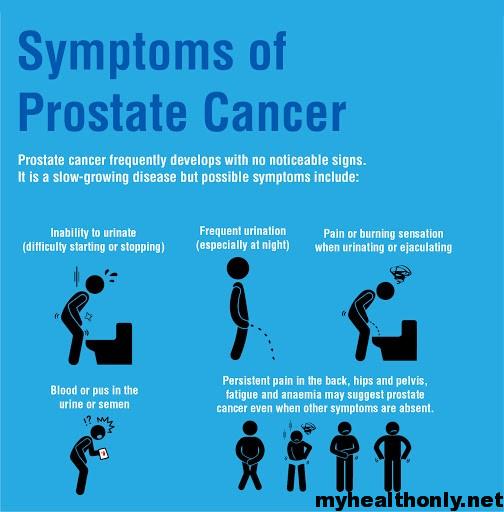

Symptoms of Prostate Cancer, Risk Factors and Causes – My Health Only

Prostate cancer is now the most common form of disease in UK – the 7 …

Prostate cancer symptoms: Pain in the back, hips or legs can indicate …